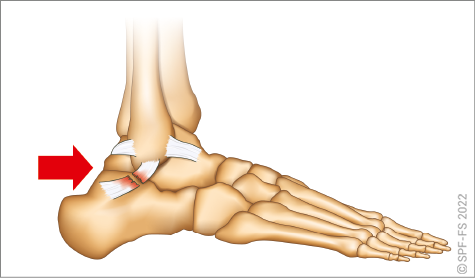

Les membres inférieurs sont chacun formés de trois segments :

Figure 2-13 : le membre inférieur

La hanche est l'articulation qui relie la cuisse au bassin. Le genou relie la cuisse à la jambe et la cheville la jambe au pied.

Ce dernier comporte cinq orteils numérotés de 1 à 5 de l'intérieur vers l'extérieur. Les phalanges sont numérotées de P1 à P3, dans le sens allant du talon vers l'ongle.